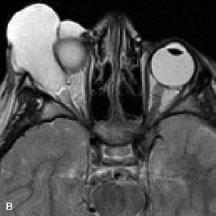

On MRI, uveal melanomas have a typical appearance that helps to differentiate them from other primary and secondary intraocular tumors as well as choroidal detachments. Pigmented melanomas are hyperintense on Tl-weighted images, hypointense on T2-weighted studies, and hyperintense on proton density–weighted examinations (Fig. 24).30,31,50,80–82 These signal characteristics have been attributed to the paramagnetic properties of melanin because of stable free radicals that shorten the T1 and T2 relaxation times. Moderate enhancement is seen on postgadolinium T2-weighted images. Gadolinium-enhanced T1-weighted images are particularly sensitive in detecting choroidal melanomas.83 MRI may be less sensitive in detecting extrascleral extension of tumor than echography performed by an experienced ultrasonographer.84

Fig. 24. A. T1- and (B) T2-weighted MR scans demonstrate a small nodular intraocular mass (arrows) that is very hyperintense on the T1-weighted scan and hypointense on the T2-weighted image. This signal intensity pattern is due to the presence of free radicals within melanin granules. C and D. Postcontrast fat-suppressed T1-weighted scans demonstrate homogeneous intense enhancement of the lesion and no evidence of seleral penetration or optic nerve invasion.